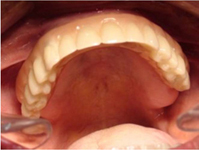

Bezzubá čelist

Pevné můstky – lepené nebo šroubované

Bezzubá čelist je hlavní indikací pro ošetření pomocí implantátů. Zejména celkové zubní náhrady v dolní čelisti mají velice nízkou stabilitu a držení díky velkému úbytku kosti.

S pomocí zubních implantátů můžeme díky různým kotevním systémům (třmeny, kulové hlavy, Locatory) zajistit stabilitu a držení protézy nebo při použití většího počtu implantátů zhotovit pevné náhrady – můstky nalepené nebo našroubované na pevno na implantáty.

S těmito typy náhrad můžeme dosáhnout perfektní funkci, výbornou estetiku, fonetiku a současně zajistit u pacienta možnost dobré hygienickou péče a čištění, která je pro životnost implantátů velice důležitá.